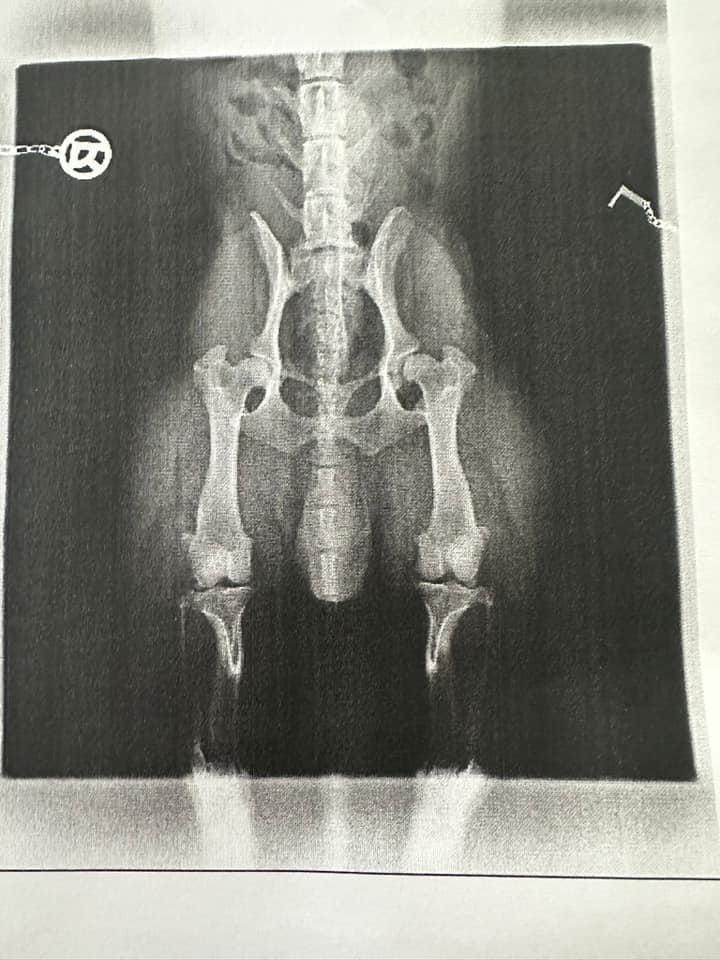

This document presents a detailed analysis of corgi hip x-rays, offering a systematic examination of the radiographic data collected from various subjects. The study is focused on the utilization of x-ray imaging to assess the anatomical structure and integrity of the hip joints in corgis, which is critical for the early identification and quantification of dysplastic changes.

The images have been evaluated using established radiographic protocols and standardized scoring systems, including the Orthopedic Foundation for Animals (OFA) criteria. These metrics provide a quantitative basis for assessing hip conformation and diagnosing potential anomalies. Through this analysis, the data aims to contribute to a more objective understanding of hip joint health and to support future research in veterinary orthopedics.

In the following sections, a curated list of hip x-rays is presented alongside pertinent observations and discussion of the imaging findings (added at a later point).

Mild / Moderate